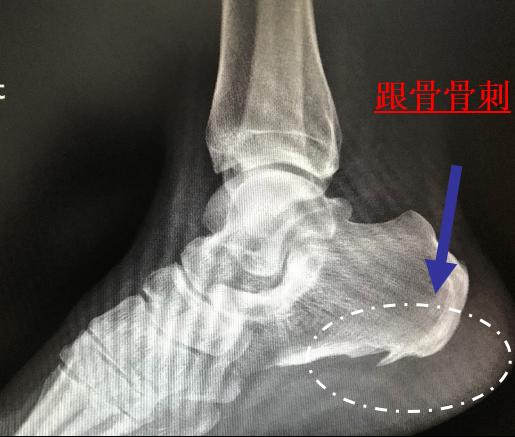

足跟痛(跟痛症)在中老年人群*特中**别常见,主要表现为足底刺痛感,负重行走加重,休息减轻,给患者生活和工作带来极大不便。本病的发生与劳损和退化等关系密切,多见于中老年,男多于女,单侧或双侧均可发病,也可发生于频繁体育运动的爱好者。足跟痛在临床上主要包括跟骨骨刺、跟部滑囊炎、跟腱炎、足底脂肪垫炎等。

图片来源于广州市中西医结合医院骨科